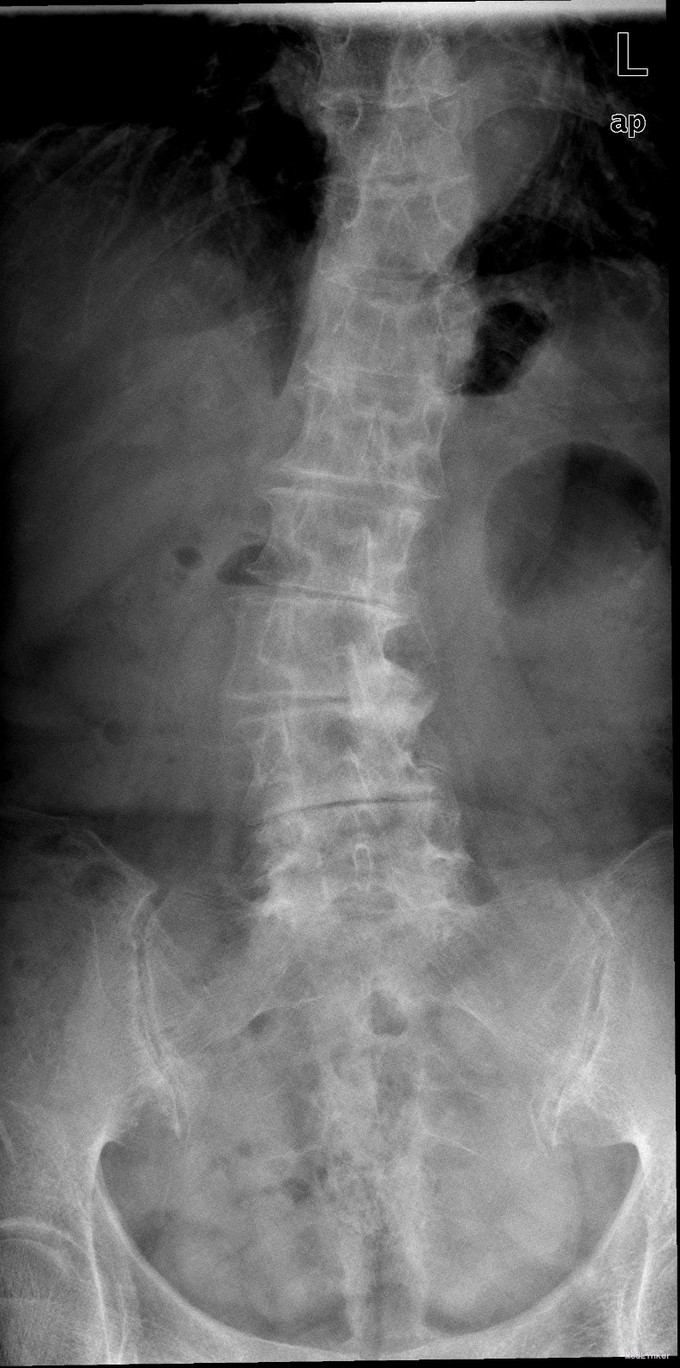

查体:脊柱无明显侧弯,腰背部无压痛,双下肢麻木酸痛,可牵连至脚跟。肌力肌张力可。腰部活动可,前屈后伸时感酸痛,无力。左侧直腿抬高试验阳性。 辅助检查:X线平片:腰椎侧弯前屈,L3椎体轻度滑脱,各椎间隙狭窄,腰椎退行性改变。 MRI:L4-5,L5-S1椎间盘膨出,L2-3,L3-4,L5-S1椎间隙狭窄,S2-3水平骶管内蛛网膜囊肿,腰椎序列不稳定,生理曲度局部后凸。

诊断:1 脊柱侧弯 伴不稳 2椎管狭窄 治疗: 前期微创腰椎侧路融合手术+后期 微创后路经皮内固定